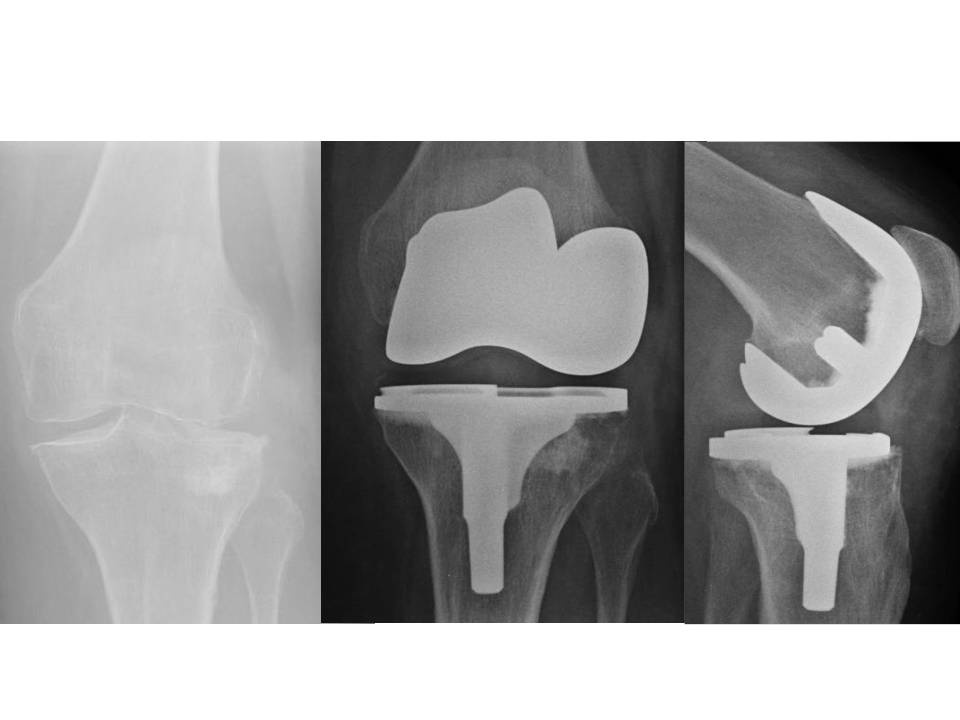

Hamburg, Deutschland) implantiert wurden. Für den Zuschnitt der Femurkondyle und des Tibiaplateaus wurde in der Gruppe mit dem PMI-System das System VisionaireTM (Smith&Nephew, Hamburg, Deutschland) genutzt. Im Zeitraum zwischen Januar 2008 und Dezember 2015 wurden im Hause 15 Patienten mit einer posttraumatischen Kniegelenksarthrose endoprothetisch versorgt. Hiervon waren zwei Patienten prä- und postoperativ auswertbar. Eine 63-jährige Patientin mit posttraumatischer Arthrose nach Tibiakopffraktur (Abb. 1) wurde mittels PMI-System versorgt (Abb. 2). Ein weiterer Patient (72 Jahre alt) wurde mit herkömmlicher Implantation versorgt (Abb. 3). Die Daten der Outcomes wurden mit hauseigenen Daten von 87 Patienten mit herkömmlicher Implantation und 84 Patienten mit PMI-gestützter Implantation verglichen. Das Durchschnittsalter der Patienten lag bei 71 respektive 66 Jahren. Das funktionelle Outcome wurde anhand des Oxford Knee Score und des Bewegungsumfanges beurteilt. Das radiologische Ergebnis wurde über die Veränderung der Knieachse sowie durch Bestimmung des medialen proximalen Tibia- und des distalen lateralen Femurwinkels (MPTA bzw. LDFA) in der Ganzbeinstandaufnahme sowie in der Messung des Slope in der seitlichen Aufnahme des Kniegelenks beurteilt. Es erfolgte die deskriptive Statistik mit Ermittlung von Maximum, Minimum, Mittelwert und Standardabweichung. Die Signifikanzprüfung erfolgte mittels Mann-Whitney-U-Test, wobei ein p-Wert von < 0,05 als signifikant angesehen wurde. Die statistische Auswertung aller Parameter erfolgte mit SPSS (Version 21.0).

Der Patient mit herkömmlich versorgter posttraumatischer Gonarthrose hatte postoperativ einen MPTA von 83° sowie einen mLDFA von 98°. Der Slope lag bei 12,4° und die Lastachse kreuzte das Tibiaplateau 7 mm medial des Fujisawapunktes. Den radiologischen Verlauf zeigt Abbildung 3.